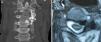

We report a case of a 74-year old woman who was admitted to our hospital with complaints of progressive left hemibody weakness and cervicalgia. Neurological examination disclosed mild left-sided hemiparesis and left torticollis. Computed tomography and magnetic resonance imaging of the cervical spine revealed an expansive lesion affecting the left C3-C4 facet joint. The patient underwent a posterior C3 and C4 hemilaminectomy, complete excision of the lesion and instrumented posterior cervical fixation. Histological examination confirmed the diagnosis of osteochondroma. After surgery her symptoms improved progressively with no neurological sequels.